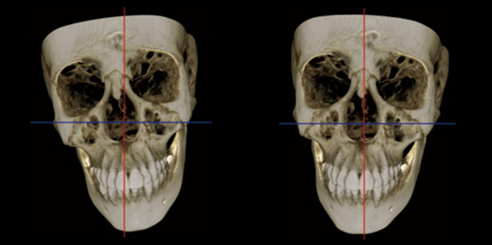

CT / CEPH / PAN Dental CBCT Functions

The LargeV CBCT supports CT, CEPH, and panoramic imaging in one compact system.

It delivers sharp, high-contrast images that reveal every dental structure with exceptional clarity.

Three Scan Modes of Dental CBCT Imaging System

Additionally, the system provides three flexible scan modes to match clinical needs. Multiple focus layers in panoramic imaging fit each patient’s dental arch perfectly.